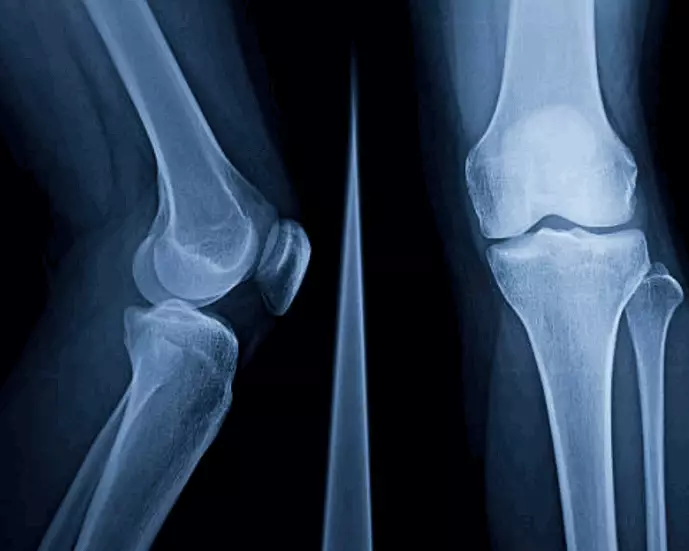

示意圖設計圖片

張勇表示,骨刺可以理解為骨骼的老化,當骨骼與骨骼之間的軟骨經長久的磨損、脫水及退化,便會導致骨質或骨骼異常增生而形成「骨刺」。

如果壓逼或摩擦到其他骨骼、韌帶、肌腱、神經等軟組織,就可能造成磨損與疼痛。

骨刺最常見出現的部位,包括了脊椎、肩膀、手部、膝蓋與腳部關節等,腰背痛等,便是很普遍的病例。